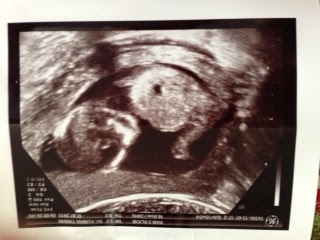

Bu hafta seni görmek bana iyi geldi. Yine o kadar tatlıydın ki… El ve ayak parmaklarını saydık. Ellerini daha net görmek için Kübra Hanım biraz bastırdı. O an on parmağını da açtın. Çok hoşumuza gitti. Biliyorum, rahatsız olduğunu hissettim ama ellerini görmek de harikaydı. Beynini de gördük. Çok bir şey anlamasam da o da iyiydi ☺ Aslında nereni görsem hoşuma gidiyor. Bayılıyorum sana. Şu an 13+4’teyiz. 16 haftalık olduğunda geri kalan testlerimizi yaptıracağız ve cinsiyetini öğreneceğiz. Annenin karnı da yavaş yavaş belirmeye başladı. Ne kadar büyüyeceğini tahmin edemiyorum. Bu hafta da kilo almadım. Ama senin ağırlığın ve boyun tam da olması gerektiği gibi seyrediyor. Bu iyiye işaret…